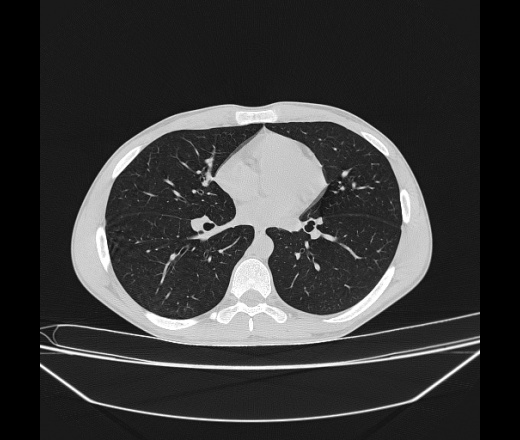

Молодой парень 18 лет, призывник, при прохождении ФЛС на верхушек левого легкого выявили очаги средней интснисвности с нечеткими контурами, тяжи. Сделали бок и томограммы 6-7-8. Везде описывают как очаговый твс. Вижу только перибронхиальный фиброз. Что за изменения в бронхах, указано нижи стрелками, тоже перибронхиальный?

Не стал бы говорить об очагах. Акцентировал бы не на фиброзе, а на тракционных бронхоэктазах. Не обязательно они результат tbc бронхов, но проверить не помешает.

Иван, пациент ведь уже "направлен с ОПТД", так?surprise Возвращайте его назад с заключением о возможном микобактериозе. Остаточные поствоспалительные ( посттуберкулёзные?) в дифряд.Очаговый твс с неясной активностью они уже себе "нарисовали", как я поняла.

+1 за микобактериоз.